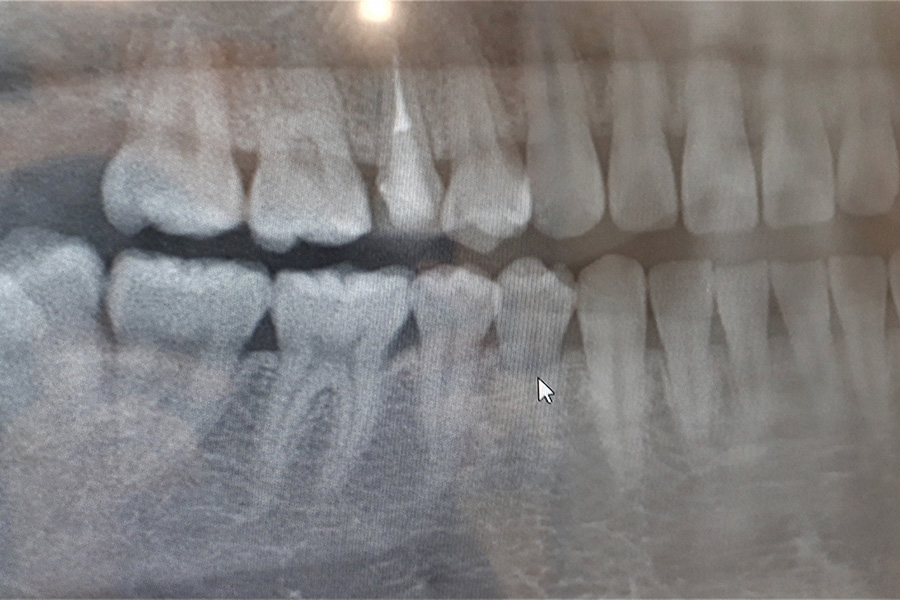

当院では必要に応じて歯科用レントゲンを活用し、歯の根や親知らずの状態を把握したうえで、正確な診断と処置を行っています。当院での処置が難しい手術が必要となる場合には、適切な医療機関をご紹介させていただきます。

親知らず

親知らずとは、10代後半から20代にかけて生えてくる奥歯のことです。

あごのスペースが足りず、斜めや横向きに生えるケースも多く、周囲の歯に悪影響を及ぼすことがあります。違和感や痛みがある場合は、早めに受診して状態を確認しましょう。